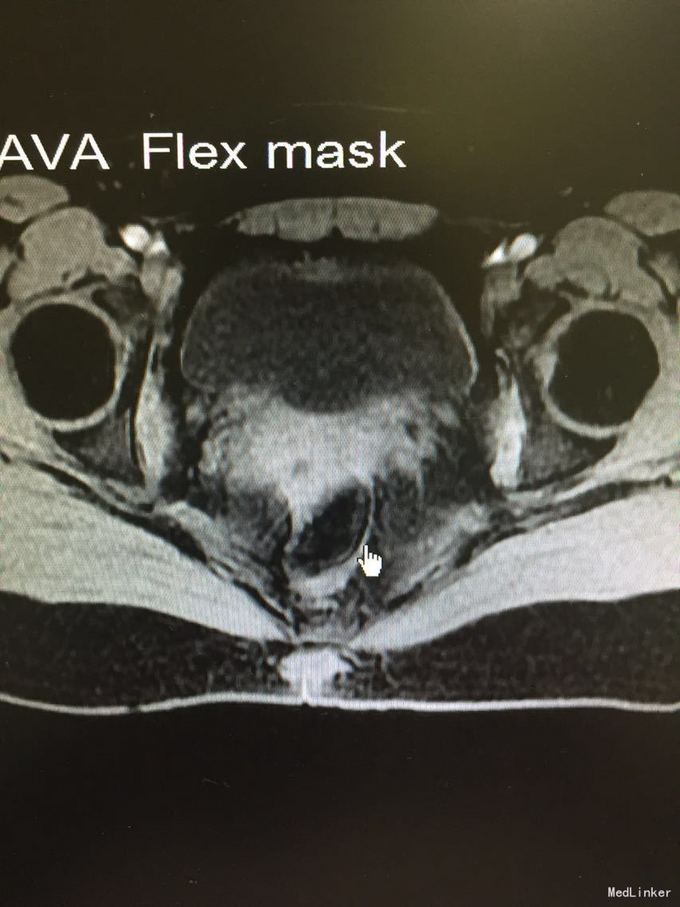

骶尾部稍红肿,隆起肿物,大小约4.5X3.0cm,无明显波动感。 盆腔MR:腰骶尾部感染性病灶可能。

骶尾部脓肿,保守治疗后症状缓解,暂予出院。

脓肿未成形,可予保守治疗,手术效果差,切口不易愈合。